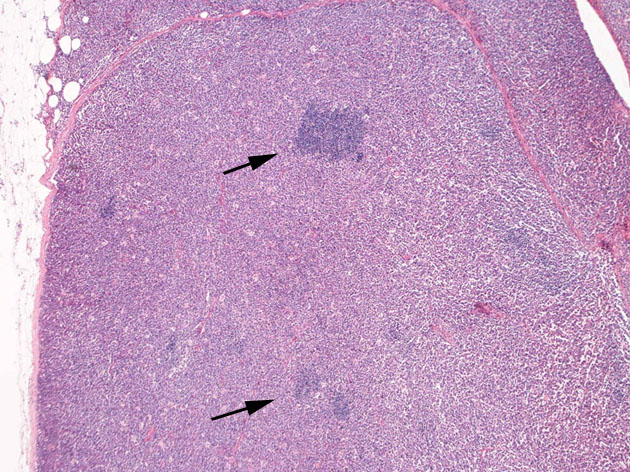

罹患リンパ節の基本構造は消失し腫瘍細胞のびまん性増殖で置換されている。非腫瘍性の小リンパ球(CD3+, CD4/8+)が濾胞様に散在して残る(Fig.01)。不整型または類円形の明るい核をもつmedium-sizeのリンパ球様細胞が密に増殖している。細胞質は乏しい(Fig.02)。CD68陽性macrophageが多く混在する部分が認められた(Fig.03)。

residualfollicle01.jpg

Fig.01Fig.02Fig.03